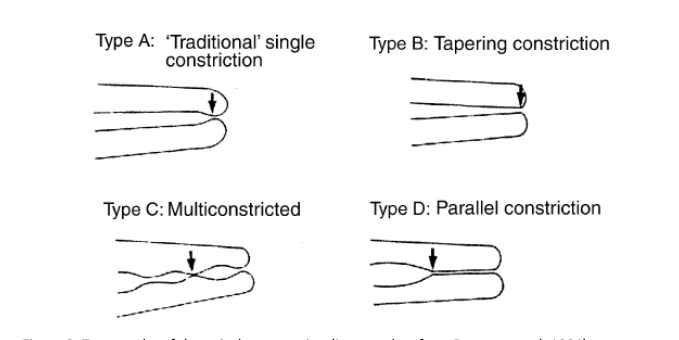

The narrowest part of the canal is the apical constriction or minor foramen. From this point the canal gradually widens to terminate at the apical foramen or major foramen (Figure 1).

- Dummer et al (1984) classified the apical constriction into four types (Figure 3). Estimating the working length using radiographs could lead to under-preparation of type B and over-preparation of type D

Figure 3: Topography of the apical construction (Image taken from Dummer et al, 1984) - Radiographs have several limitations that can cause difficulties and errors in WL determination